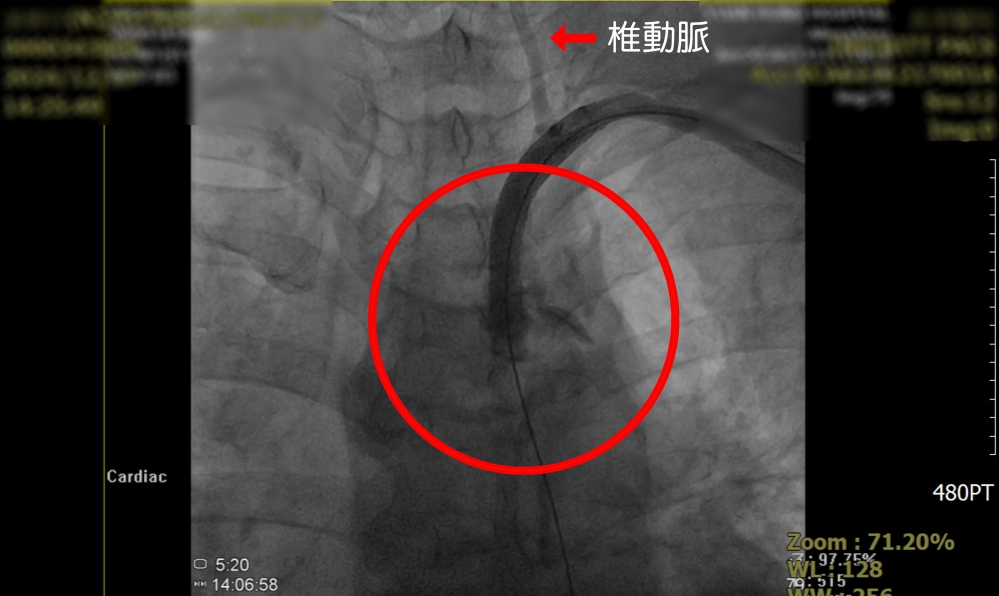

這名中年女病患的頭暈症狀,持續多年,她是洗腎患者,半年多前因洗腎血流量不足,向員榮醫院心臟外科主任賴金湖求助,賴主任為患者打通洗腎廔管,但動脈壓力仍低,頭暈仍在,賴主任推測罹患「鎖骨下動脈竊血症候群」,經血管攝影確定後,為患者施行導管微創血管成型術及支架置放,終將解決患者困擾多年的頭暈症狀。

賴主任說,人體頭部的血液分別由前方左右兩側頸動脈及後方脊椎動脈供應,正常血流方向是由心臟向遠端流動,但「鎖骨下竊血症候群」患者,因鎖骨下動脈近端阻塞,向左側腋下動脈及左側椎動脈血流量不足,患者未查覺有異常感覺,但劇烈活動時,左手血管需要較多血流量,由於左側鎖骨下動脈供應的血流量不夠,致發生左側椎動脈血液,逆流供應左手需要的血量,稱為「竊血症候群」。因左側椎動脈原本供應腦幹、小腦和部分大腦,一旦血流量下降,會造成頭部缺血,患者就出現頭痛、頭暈等症狀。